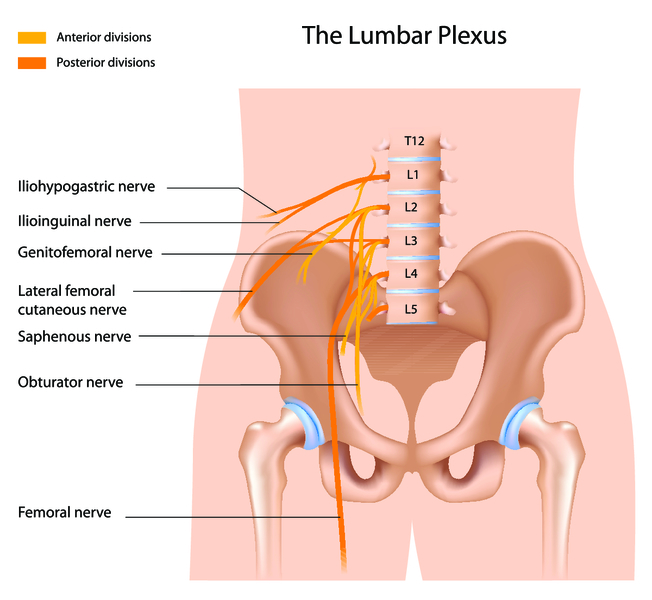

Болезнь Рота (или парестетическая мералгия) – это одна из самых частых разновидностей туннельного синдрома, вызываемая сдавлением латерального кожного нерва бедра в области передней подвздошной кости или паховой связки. Она проявляется не столько болью, сколько появлением неприятных ощущений различного характера. Страдающий при этом виде невралгии нерв формируется из нескольких ветвей, выходящих из спинного мозга, проходит по каналу и заканчивается в области колена. Он обеспечивает чувствительность передней поверхности бедра.

По данным статистики, это заболевание чаще наблюдается у мужчин 50-60 лет или беременных. И частое развитие болезни Рота во многом связано с анатомическими особенностями расположения латерального кожного нерва. Он проходит по туннелю и часто сдавливается при его трении в области паховой связки или возле подвздошной кости во время наклона туловища вперед или движения ног. На своем пути нерв кроме этих «препятствий» проходит сквозь широкую фасцию бедра и может поражаться еще и на таких уровнях: